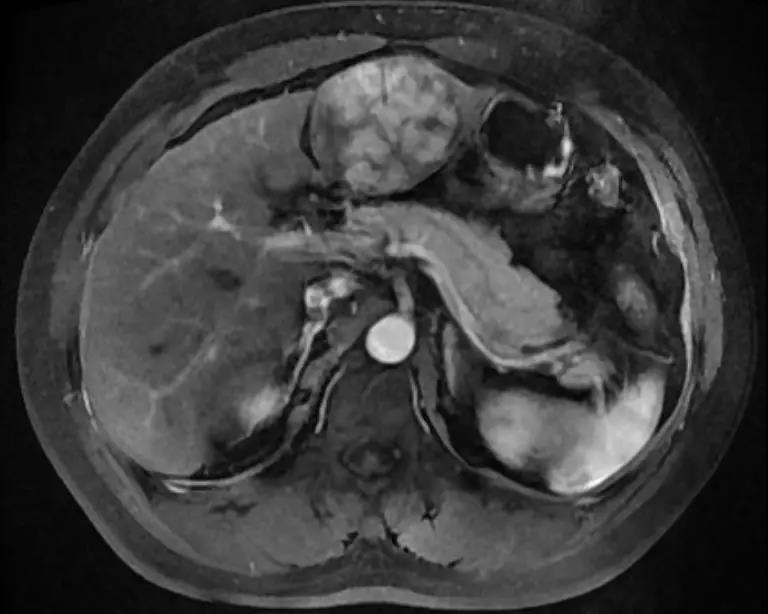

肝胆 MR 平扫弥散+增强:左肝内占位,肝癌首先考虑,请结合临床。附见:双肾囊肿。

动脉期